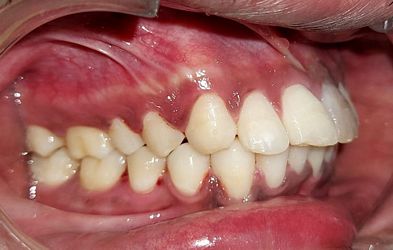

Intra-oral : Pre-treatment : Right Lateral View

Intra-oral : Post-treatment : Right Lateral View

Intra-oral : Pre-treatment : Left Lateral View

Intra-oral : Post-treatment : Left Lateral View

Inta-oral : Pre, Mid & Post-treatment : Right Lateral View

Intra-oral : Pre, Mid & Post-treatment : Left Lateral View